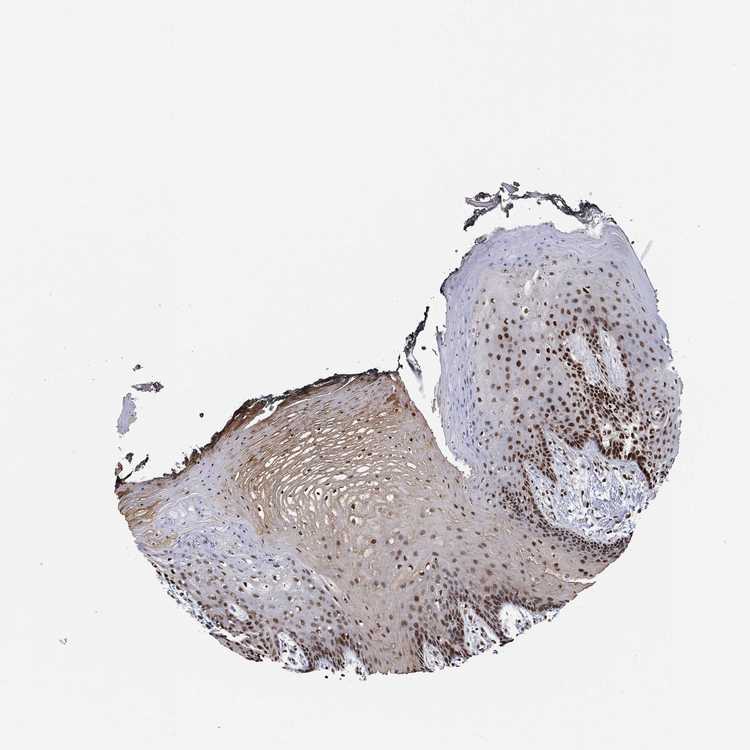

TISSUE PRIMARY DATA ORAL MUCOSA Show tissue menu

ORAL MUCOSA - Antibody stainingi

Antibody staining in the annotated cell types in the current human tissue is reported as not detected, low, medium, or high, based on conventional immunohistochemistry profiling in selected tissues. This score is based on the combination of the staining intensity and fraction of stained cells.

Each image is clickable and will lead to virtual microscopy that enables deeper exploration of all samples and also displays staining intensity scores, fraction scores and subcellular localization as well as patient and tissue information for each sample.

Antibody HPA007289

Squamous epithelial cells Medium